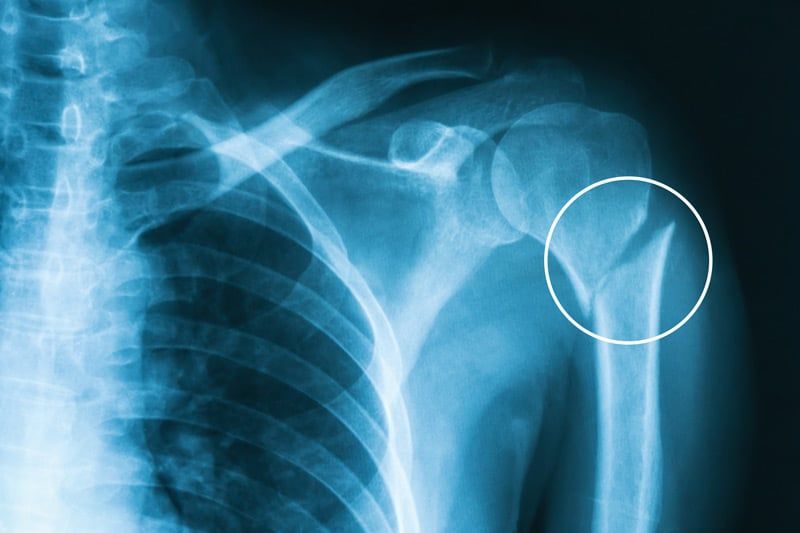

Upper limb fractures and dislocations

Upper limb refers to part of our body starting from the shoulder upto the fingers in our hands. As we use the arms and hands for routine and recreational activities like sports, they are prone for several injuries including fractures (break in the bone) or dislocations (loss of alignment of joints like shoulder / elbow) resulting in sever pain and sometimes risk to the arm / hand survival.

Rapid diagnosis and immediate treatment from a specialist like Dr Darshan Angadi who is well experienced in managing these injuries is crucial to prevent the risk of long-term complications that can occur from damage to nerve / tendon / artery or cartilage.